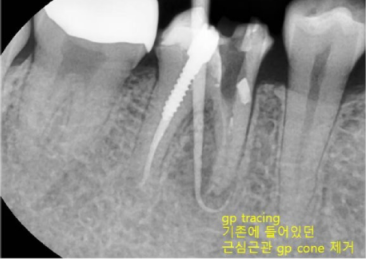

수많은 임플란트 케이스를 진행하면서도 이백점치과는 '자연치아는 그 어떤 임플란트로도 대체할 수 없다'는 확고한 철학을 가지고 있습니다. 그래서 언제나 자연치아를 살리기 위해 최선을 다합니다. 이번 사례는 타 치과에서 발치 진단을 받은 치아를 성공적으로 재신경치료하여 살려낸 고난도 케이스입니다. CASE. "뽑아야 한다던 치아, 재신경치료로 살려냈어요!" ○환자분의 고민 - 타 치과에서 이미 신경치료를 받았음에도 계속 불편감을 호소하며 내원한 환자분이었습니다. - 오른쪽 아래 치아 앞 잇몸에 고름 주머니(농양)가 생겨 있었고,  방사선 사진상 뿌리 끝에 심한 염증과 고름이 확인되었습니다. - 더욱이 이미 신경치료 후 포스트(기둥)까지 박혀있어, 타 치과에서는 이미 '발치'를 고지받은 상황이었습니다. ![]() ○ 진단: 정밀 CT 촬영을 통해 고름 주머니가 생긴 원인을 분석했습니다. 기존 신경치료가 되어있던 뒤쪽 뿌리가 아닌,  앞쪽 뿌리의 신경관에 문제가 발생하여 염증이 재발된 것을 정확히 진단했습니다. ![]() '발치 없이' 자연치아를 살리는 재신경치료 이백점치과는 고심 끝에 기존 기둥을 그대로 두고, 문제의 원인이었던 앞쪽 뿌리를 다시 신경치료하기로 결정했습니다. 1. 정교한 기존 재료 제거 : 기존에 충전되어 있던 신경치료 재료를 조심스럽게 제거했습니다. 2. 꼼꼼한 신경관 재정비 : 뿌리 끝까지 신경관을 깨끗하게 넓히고 소독했습니다. 3. 염증 해소 약재 적용 : 뿌리 끝 염증 해소를 위해 염증 완화 약재를 세심하게 적용했습니다. 기적 같은 결과, 1년 후에도 건강하게! - 3주 만의 드라마틱한 호전: 불과 3주 만에 바깥 잇몸의 고름 주머니가 완전히 없어졌고, 환자분의 모든 증상이 사라졌습니다.  이후 신경치료를 마무리하고 보철 치료까지 성공적으로 진행했습니다. - 1년 뒤에도 완벽한 경과: 1년 뒤 다시 체크했을 때, 염증은 전부 가라앉았고 고름 주머니 흔적 없이 깨끗했습니다.  심지어 염증으로 녹아있던 뼈 부위에는 새로운 뼈가 형성되고 있음이 확인되었습니다. ![]() 환자분 또한 통증 없이 건강하게 생활할 수 있어 매우 감사하다는 인사를 전했습니다. ![]() 이처럼 살리기 어렵다고 판단되던 고난도 치아를 발치 없이 살려낸 사례는 의료계 내부에서도 높은 평가를 받았습 니다. 이백점치과는 항상 환자분의 입장에서 생각하며 '발치만이 해답이 아님'을 증명하고, 자연치아 보존을 위한 최선의 노력을 다하고 있습니다. ![]()  |